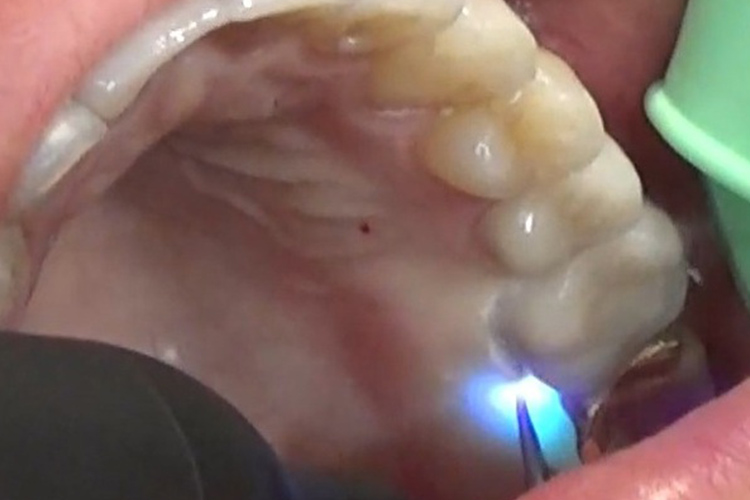

(施術風景)

深い歯周ポケットに青いレーザー光と過酸化水素水を照射し、患部を殺菌します。